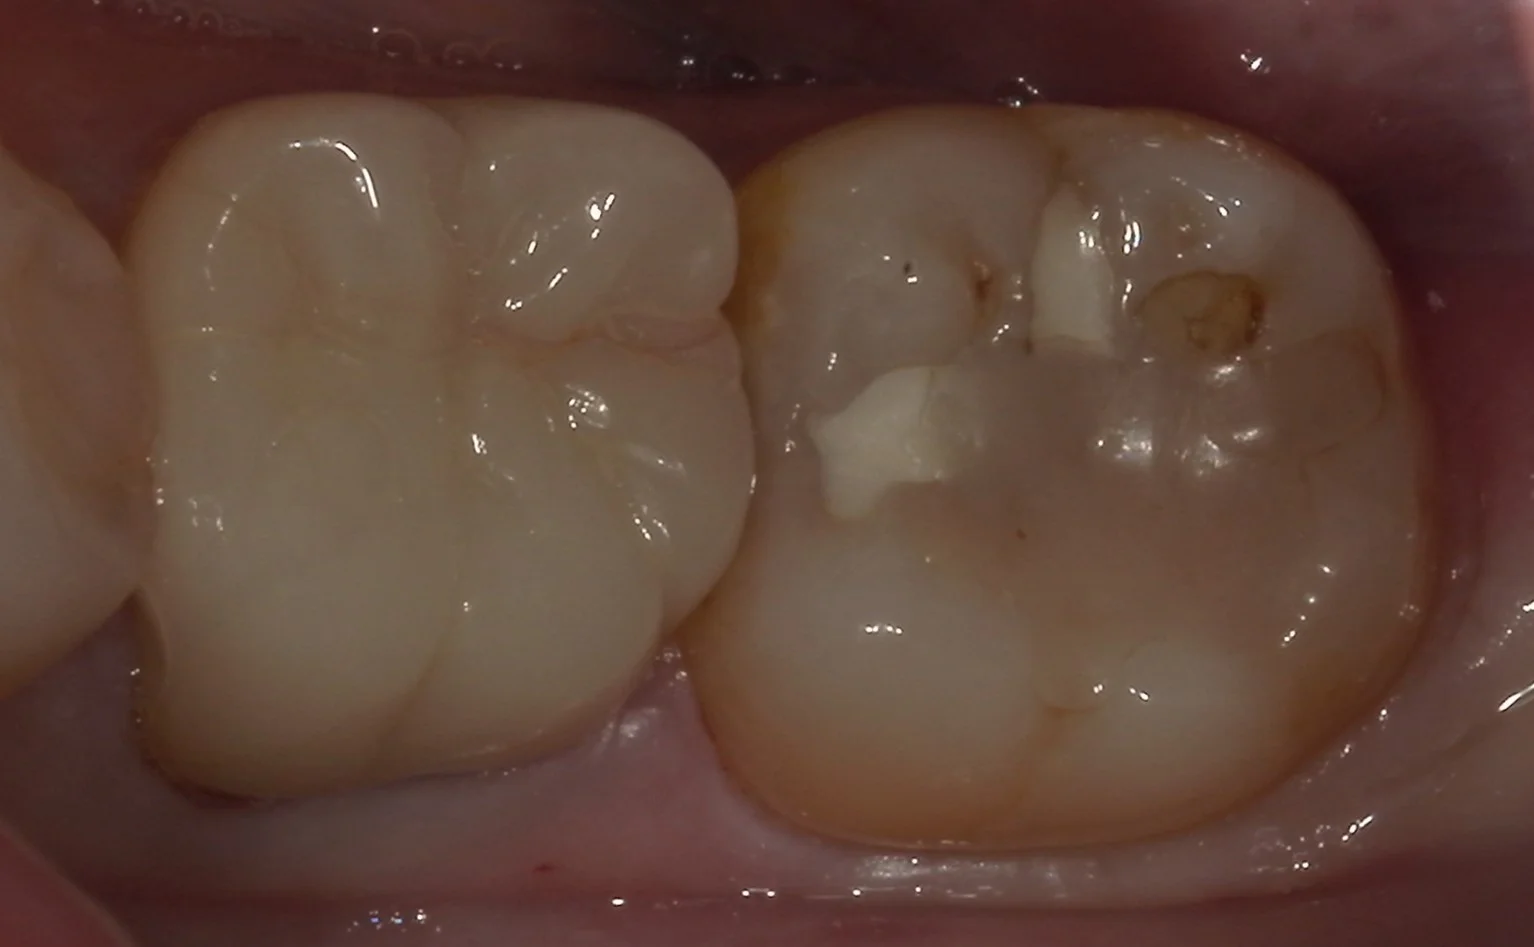

では術前の写真からです。

画面右側の部分が今回治療するところです。

どうやら前に行った処置の部分を取りきることなくそのまま上に新しい詰め物を詰めただけのようですね。

「既に硬化が完了しているものに対して強固に接着させる」というのは実は非常に困難です。

その為、実際はその隙間から中に虫歯が入り込んでいってしまうことが多々あります。